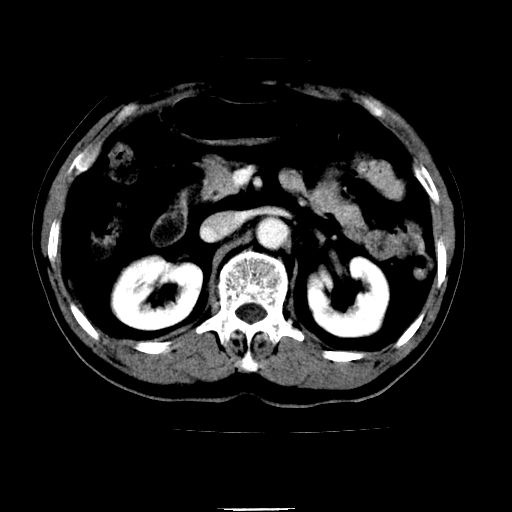

以下是引用chenqiong在2010-3-25 20:56:00的发言:[br]1、胆囊炎,胆囊息肉[br]2、肝内胆管及胆总管扩张,胆总管下端结石[br]3、十二指肠乳头旁憩室

以下是引用zxl51642在2010-3-26 10:47:00的发言:[br]胆囊炎,胆囊息肉,胆总管扩张,但未看到明显肿块,肝内胆管扩张不像恶性,炎性狭窄或阴性结石可能吧,建议mrcp,右肾小囊肿